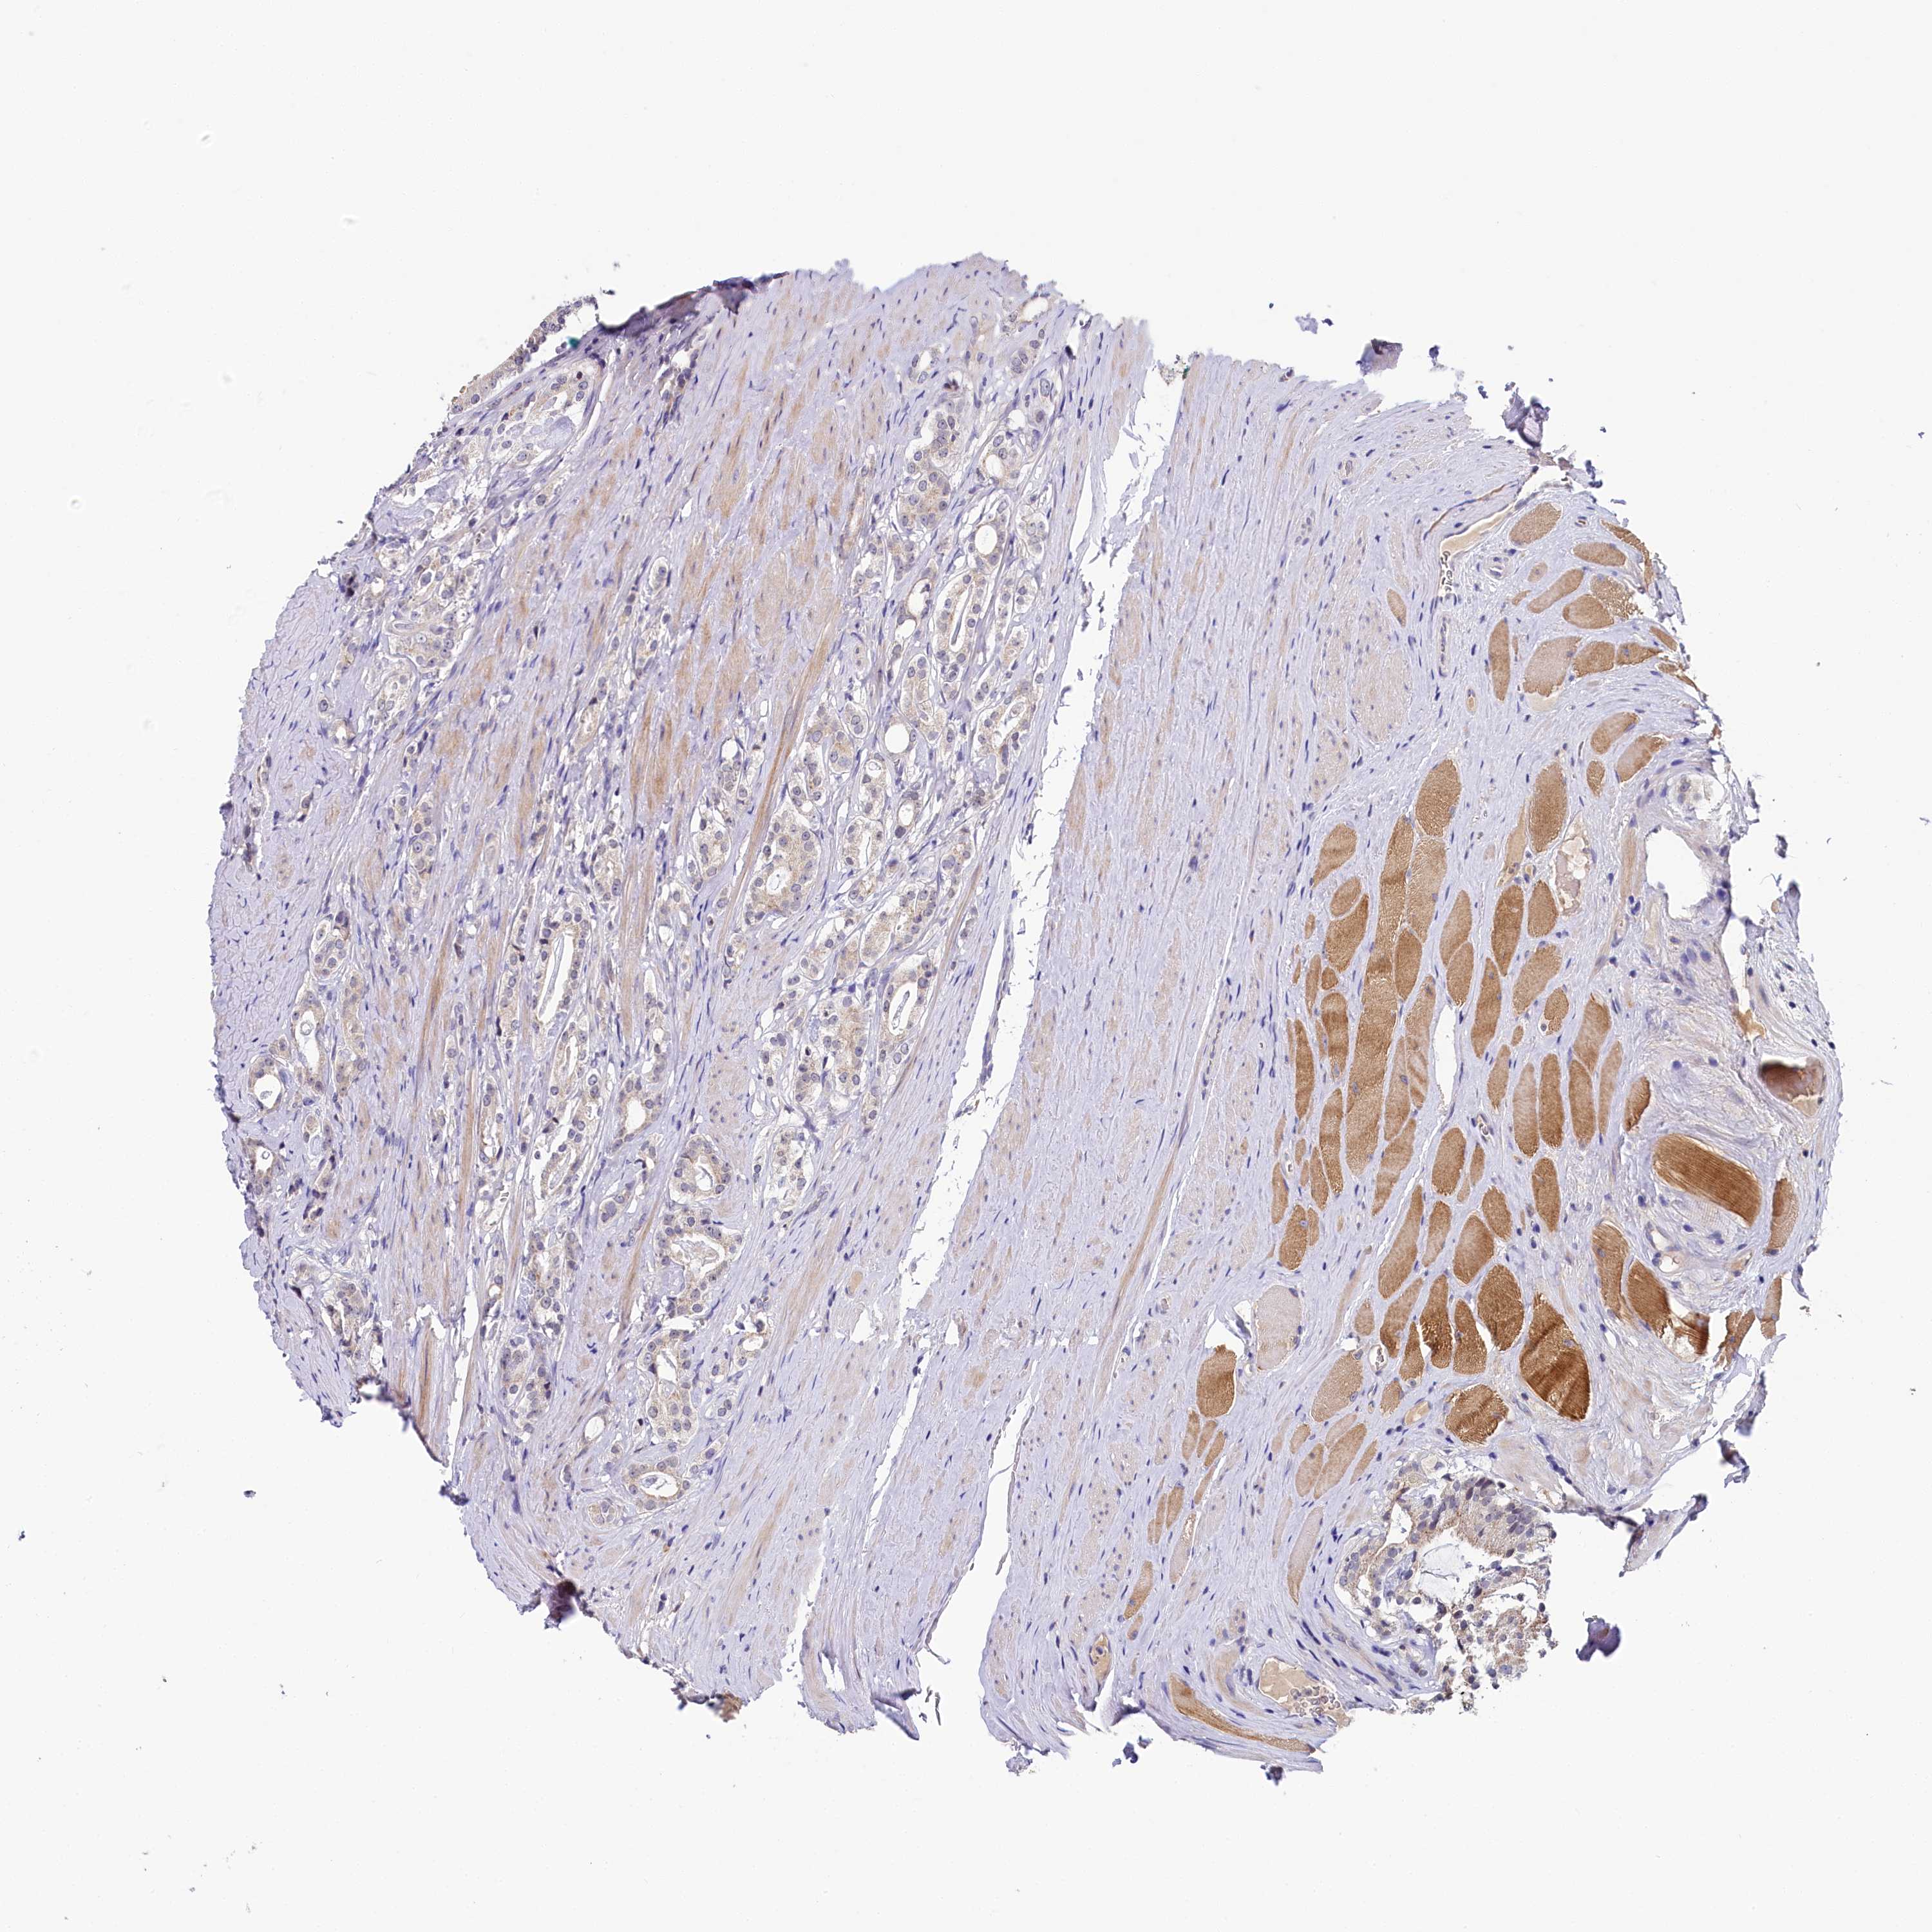

PROSTATE CANCER - Protein expressioni

A mouse-over function shows sample information and annotation data. Click on an image to view it in a full screen mode. Samples can be filtered based on level of antibody staining by selecting one or several of the following categories: high, medium, low and not detected. The assay and annotation is described here.

Note that samples used for immunohistochemistry by the Human Protein Atlas do not correspond to samples in the TCGA dataset.

Antibody stainingi

Antibody staining in the annotated cell types in the current human tissue is reported as not detected, low, medium, or high, based on conventional immunohistochemistry profiling in selected tissues. This score is based on the combination of the staining intensity and fraction of stained cells.

Each image is clickable and will lead to virtual microscopy that enables deeper exploration of all samples and also displays staining intensity scores, fraction scores and subcellular localization as well as patient and tissue information for each sample.

Antibody HPA038288

Staining

High

Medium

Low

Not detected

Intensity

Strong

Moderate

Weak

Negative

Quantity

>75%

75%-25%

<25%

None

Location

Nuclear

Cytoplasmic/membranous

Cytoplasmic/membranous,nuclear

Adenocarcinoma, High grade

Adenocarcinoma, Low grade